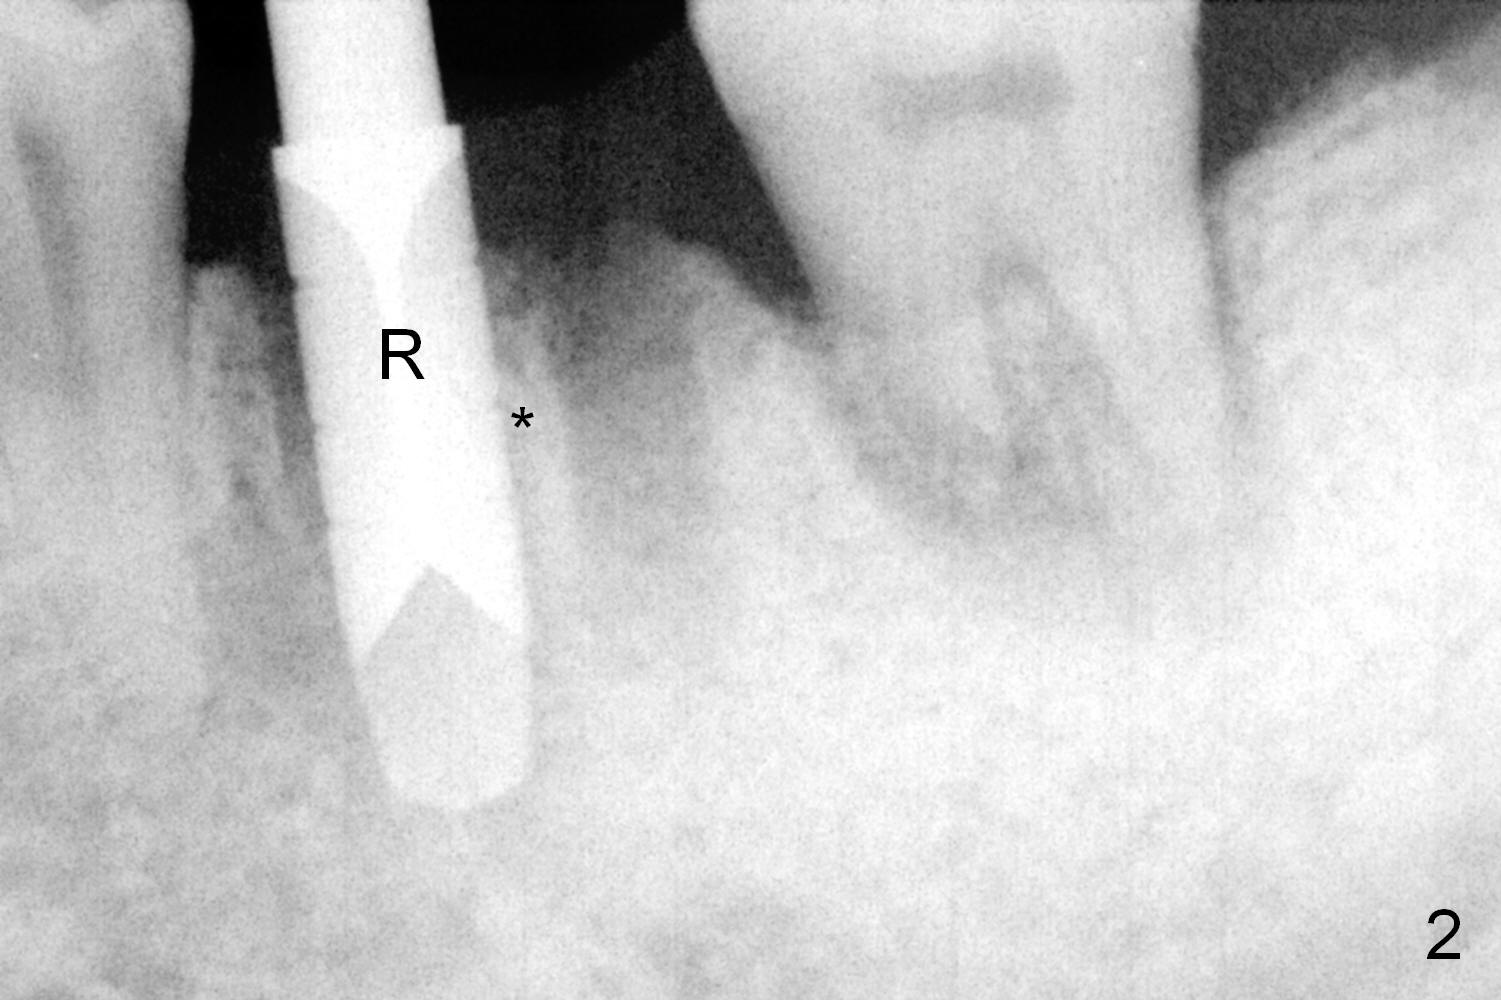

A fistula is found to be associated with the furca when the patient returns for extraction (Fig.1 <). Although the mesial socket is deeper than the distal one, no granulation tissue is curetted from the mesial. Osteotomy is set in the middle of the septum by making a slot first. When the osteotomy is enlarged by 4 mm reamer (Fig.2 R), the latter has been deviated mesial to the septum (*). By manipulating, the coronal end of 6x12 mm implant and 6.5x4(3) mm abutment (Fig.3 A) are placed somewhat in the middle of the socket. An immediate provisional is fabricated to cover the socket and bone graft (Fig.4 P). The exposed bone graft (Fig.4 *) is then covered by perio dressing. Off axial placement of the implant (Fig.5 I) and abutment (A) is striking in the immediately postop PA (Fig.5).

How to place the immediate implant in the middle of the septum? In addition to the slot in the middle, the smallest pilot drill should be used for limited depth and an early intraop PA should be taken (Fig.6). If the deviation is noted (Fig.6 red long arrow) in the septum (S), it should be corrected before using the next drill (Fig.7).